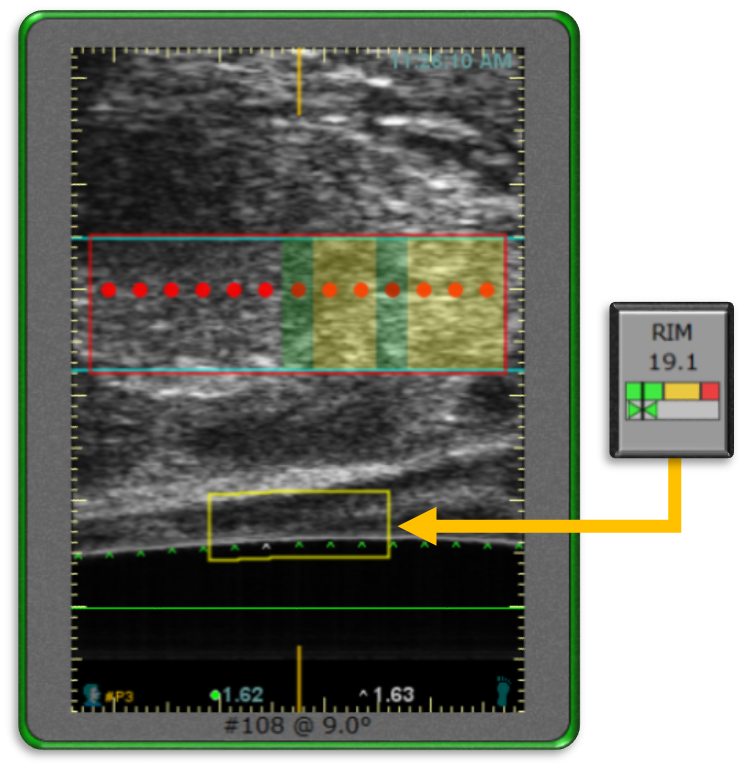

Reflectivity Index Monitor (RIM) 反射率指數監控

用於監測直腸壁中能量的積累,它以量測影像像素的明亮度來定義能量的大小。如左圖所示, RIM框內的數值代表黄色長方形框內,這個特定範圍裏的組織能量數據。黄色框則是特地擺放到即時影像和參考用切片影像重疊的位置。

在消融的過程, 系統會一直比較即時影像和參考影像的明亮度。RIM數據一直升高,表示這個範圍的能量正不斷地累積,當RIM數據到達一定的數字後,系統判斷累積的能量過高,有傷害直腸壁的疑慮,系統會自動停止消融。